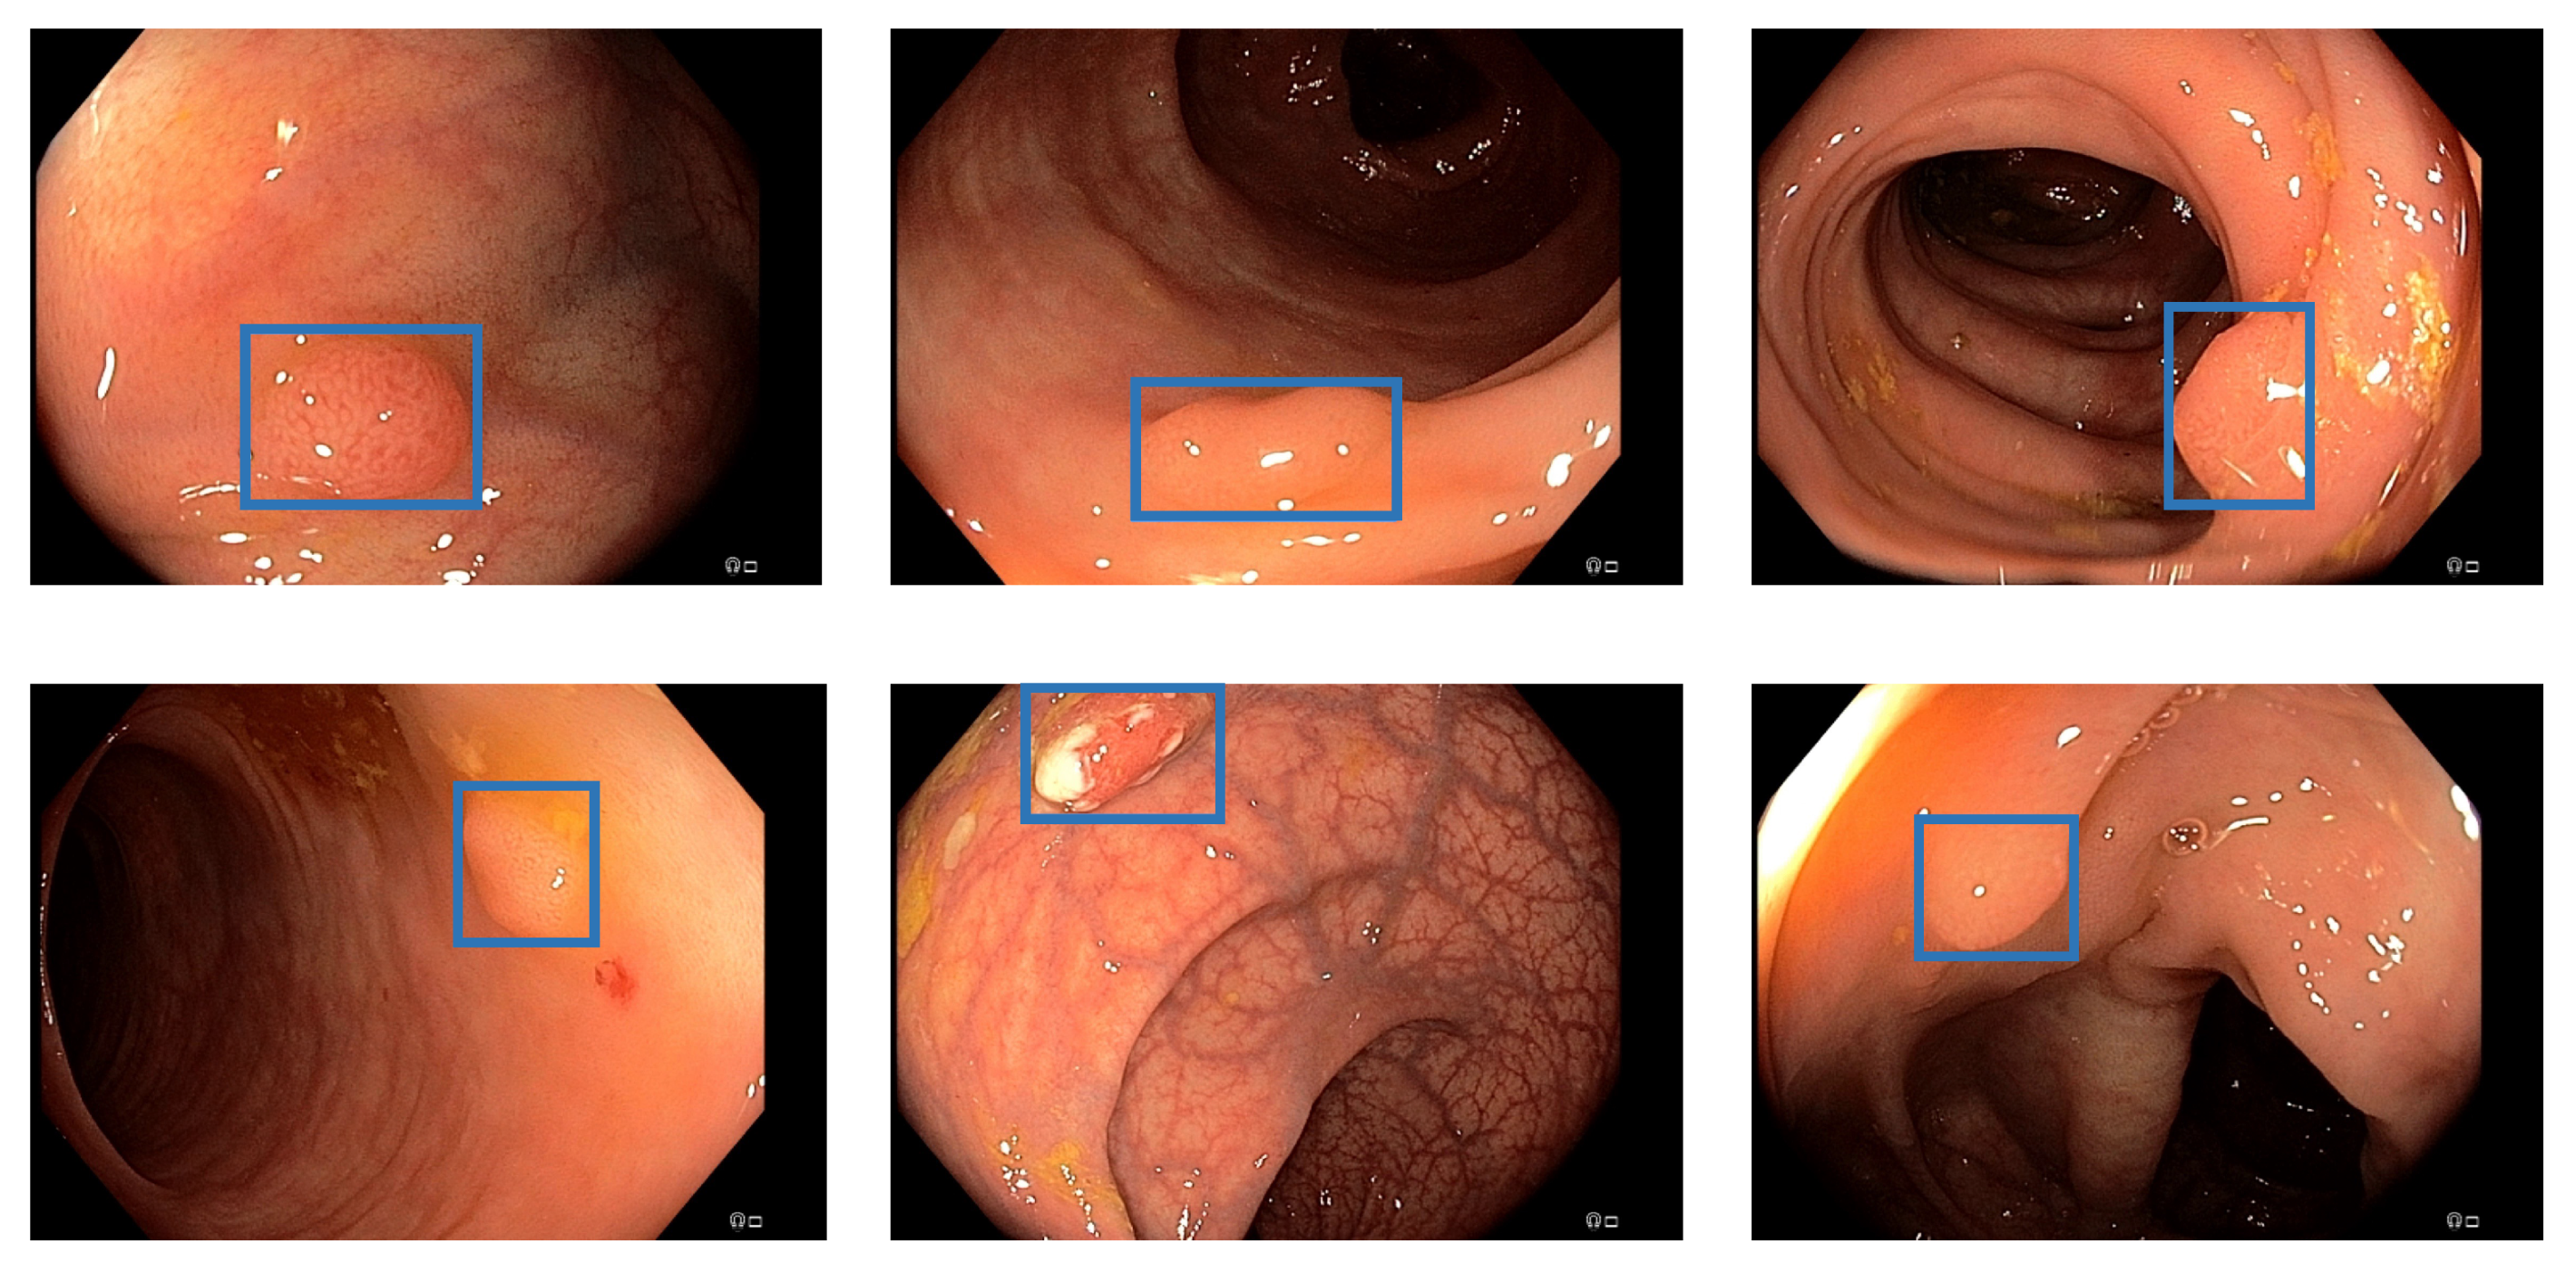

Figure 1.

Detection examples. This figure illustrated some detection examples of the polyp-detection system on our own data (EndoData).